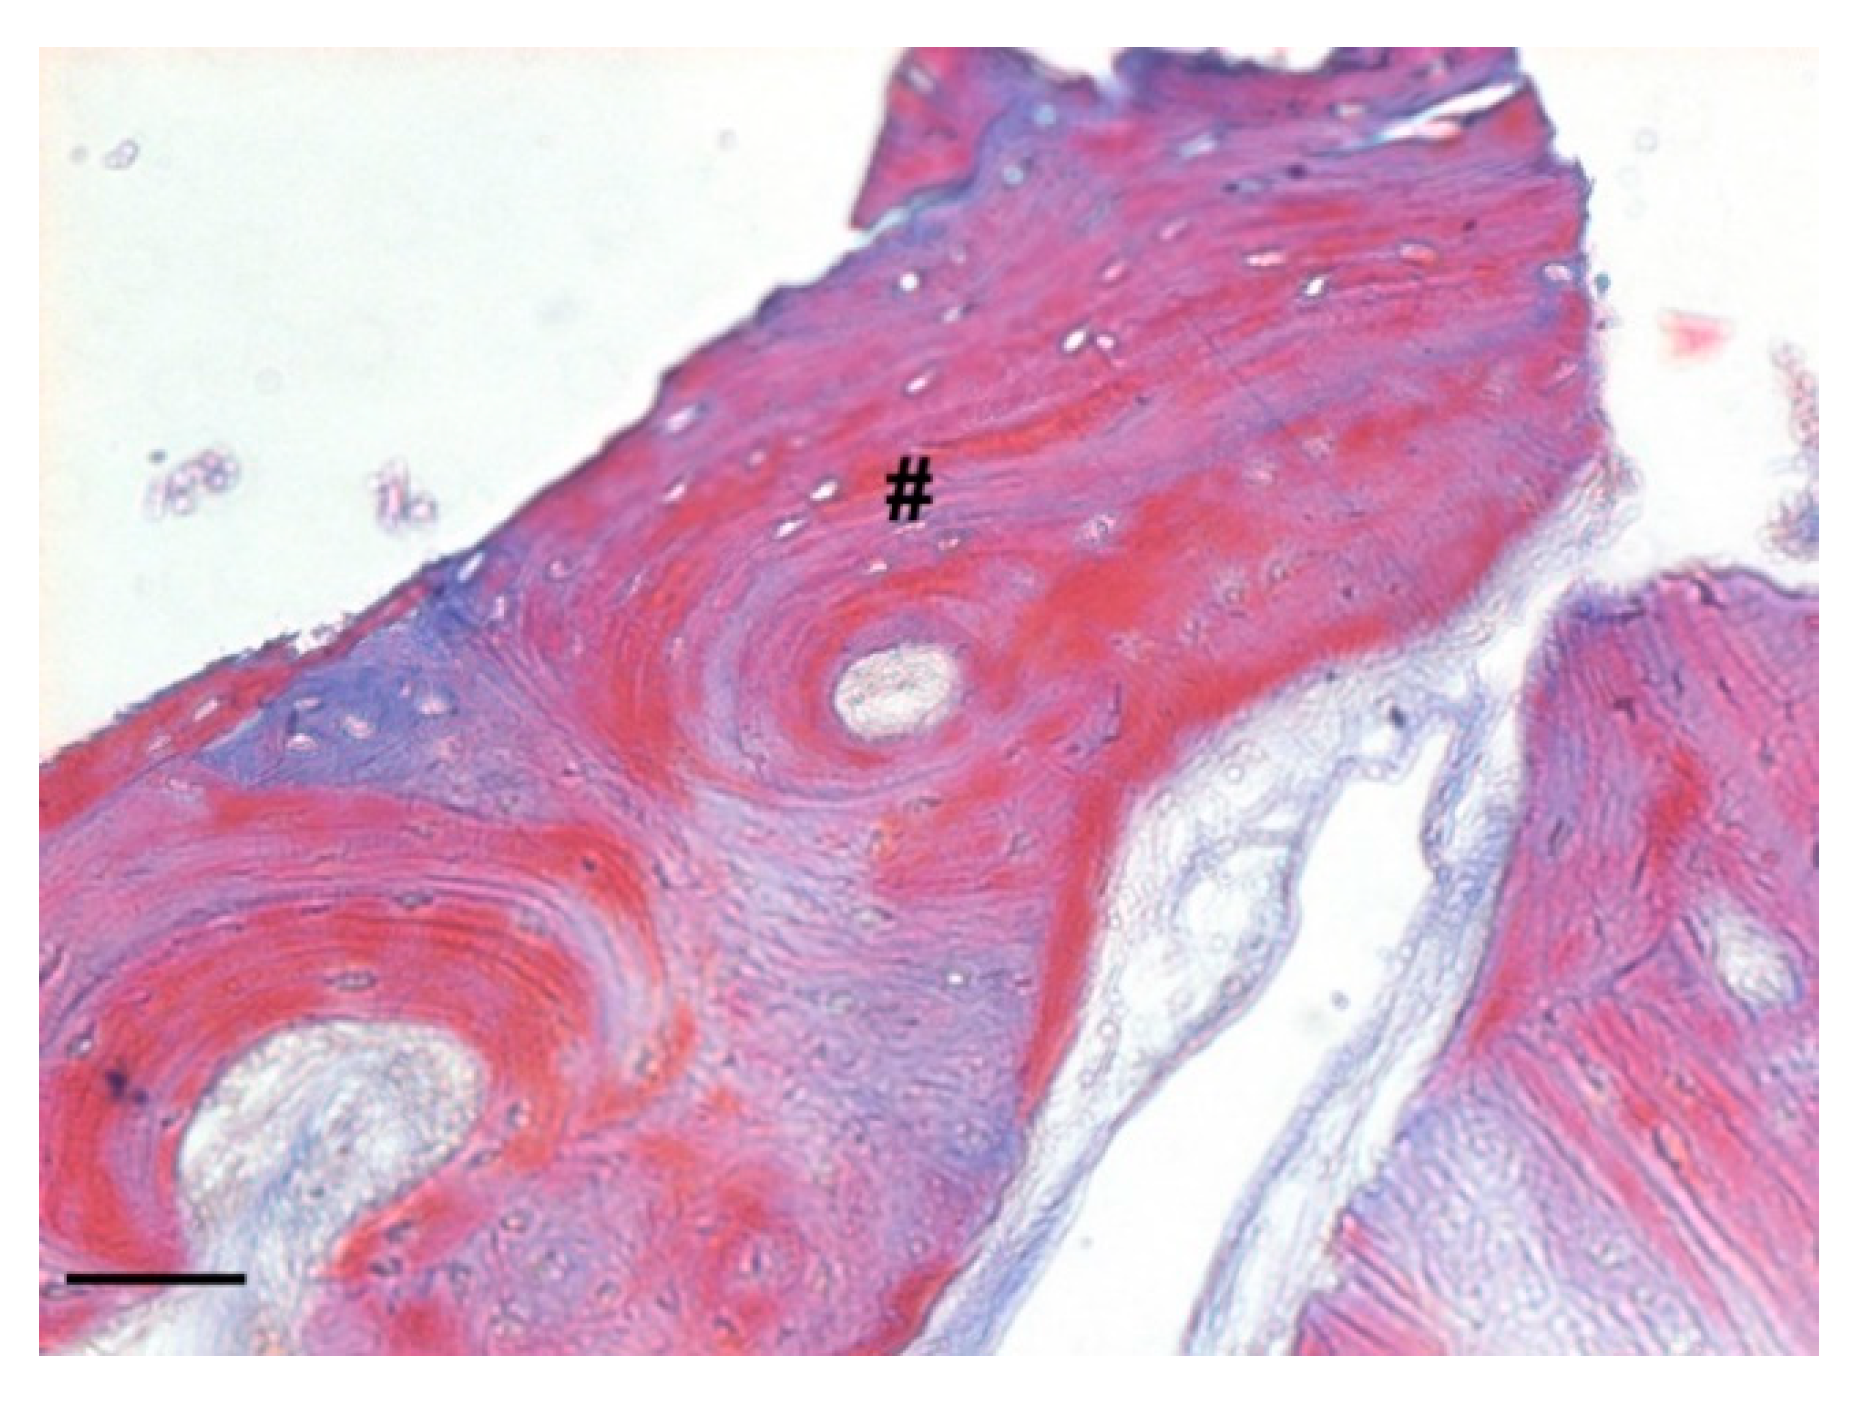

Probable rows of osteoblasts in the active phase secreting osteoid tissue could be found in close proximity to the biomaterial granules. Moreover, in the deepest areas of the sample, the presence of lamellar bone, an index of complete bone remodeling, was found (Figure 17).

Figure 17.

Detail of the bone sample stained with Masson’s trichrome staining solution (magnification 100×, scale bar 100 μm). The image shows the presence of lamellar bone indicating the complete bone remodeling (#).